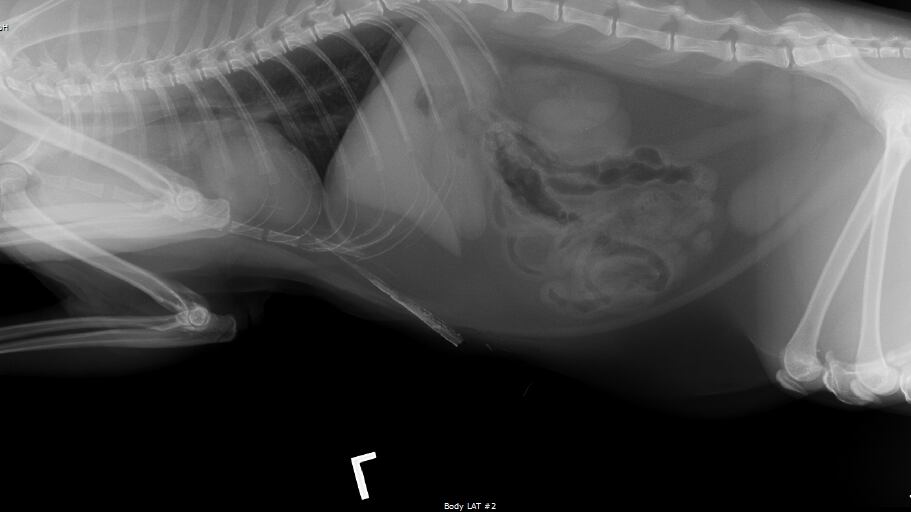

Doctors at the hospital found a very sharp stick had become stuck in the cat's abdomen near his heart.